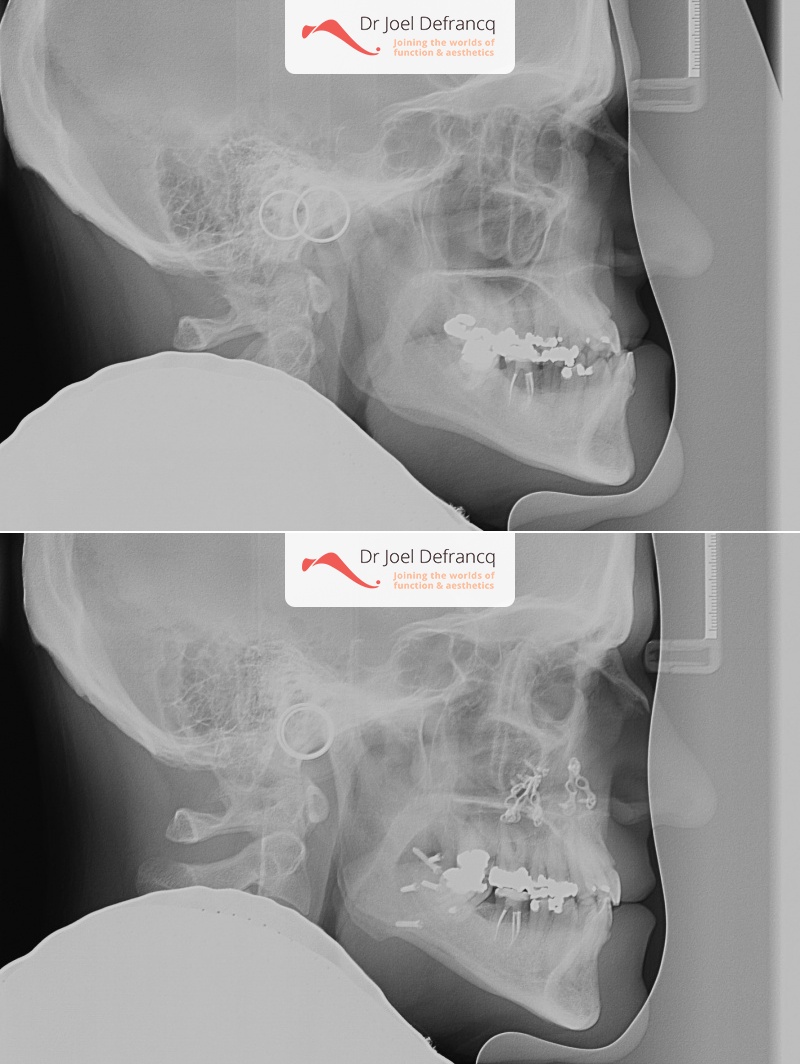

Rudy: upper jaw too far back

Diagnose van het gezicht

- Te grote onderkaak (Onderbeet)

- Te kleine bovenkaak

- Te korte bovenkaak

- Asymmetrisch gezicht

Kaakchirurgie

- Verlenging bovenkaak (Le Fort I)

- Onderkaak rotatie

- Kinchirurgie

Esthetische chirurgie

- Jukbeen augmentatie